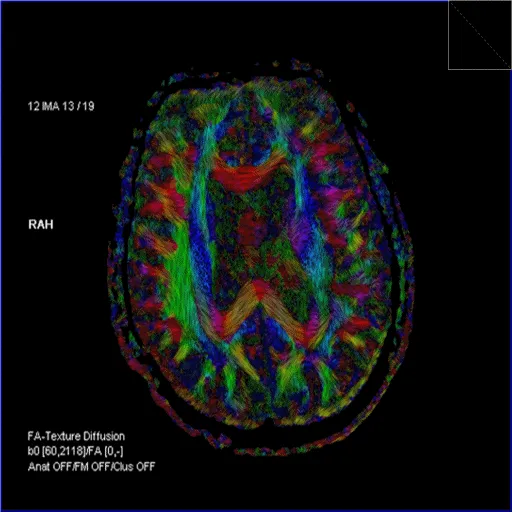

DTI & Tractography - Neural Highways Exposed

- Diffusion Tensor Imaging (DTI): Measures directionality of water diffusion in tissues, especially white matter.

- Diffusion Tensor: Describes magnitude & direction of water diffusion in 3D.

- Fractional Anisotropy (FA): Degree of directional preference (0=isotropic, 1=anisotropic).

- Mean Diffusivity (MD): Average diffusion rate.

- FA Color Maps: Visualize tract orientation:

- Red: Left-Right (e.g., corpus callosum)

- Blue: Superior-Inferior (e.g., corticospinal tracts)

- Green: Anterior-Posterior (e.g., cingulum)

- Tractography: 3D reconstruction of white matter tracts. Applications: pre-surgical planning, assessing white matter injury (e.g., TBI, stroke), neurodegenerative diseases.

⭐ DTI is used to assess white matter tract integrity and directionality, crucial in conditions like traumatic brain injury or for surgical planning near eloquent pathways.